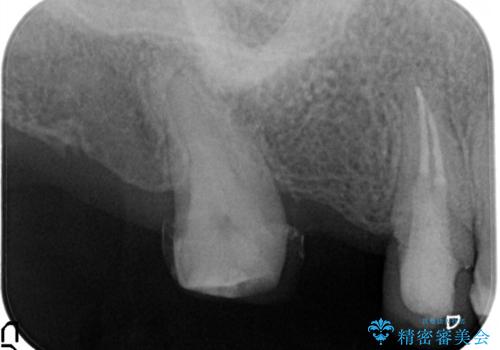

抜歯してから歯周組織が安定するまで期間がかかります。

十分に期間を治癒を待つことで審美性や清掃性の高い被せものを製作できます。